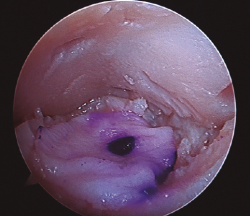

Figura 1. Lesión osteocondral de grado IIB en vertiente talar medial.

- Inicialmente procedemos a retirar el cartílago inestable, el hueso necrótico y la capa superior calcificada mediante un sinoviotomo, fresa motorizada, junto con instrumental de curetaje artroscópico (Figura 1).